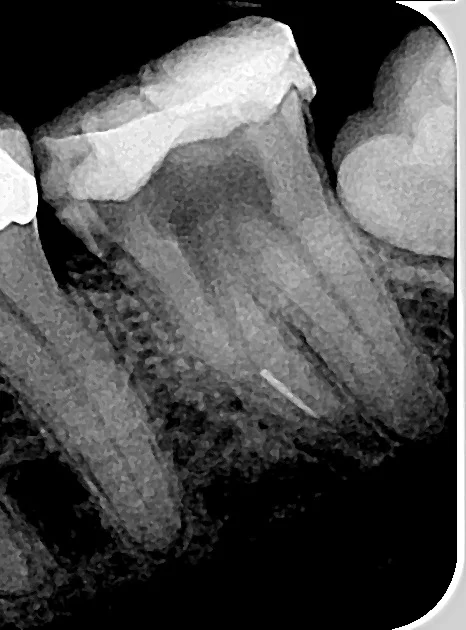

Read MoreFirst of all, I need everyone to know that it’s like stabbing myself in the eye with pins, or having a drill break off in my tooth in the middle of a root canal writing something that contains no humour whatsoever. Anybody who has followed my writing over the years knows that I sometimes write about some uncomfortable shit, but my secret weapon has always been to wrap it in funny, the same way you wrap asparagus in bacon. Humour and bacon can make the most unsavory things in life taste awesome.

Read MoreA drill bit wedged in my jaw. A huge chunk of cork hanging off my nipple. Body modifications that didn’t go as planned.

I was sitting in the dentist’s chair, gripping the leather arm rests, my jaw cranked open, enduring, as best I could, a root canal.

And then things went wrong.